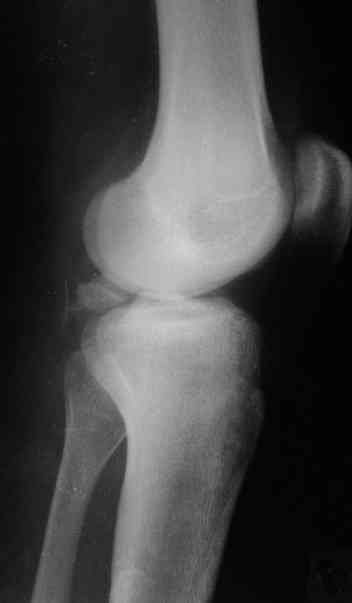

На основании небольшого личного опыта (4 пациента с отрывным переломом задне-верхнего края большеберцовой кости) и данных литературы оптимальным считаю задний доступ, упомянутый David P. Zamorano.

В 3 из 4 случаев мы применили винт, проведенный ретроградно по аналогии с фиксацией заднего края большеберцовой кости при переломах в

области голеностопного сустава. В прищепке рентгенограммы одного из наших пациентов до операции и спустя полгода. Остальные 3 наблюдения